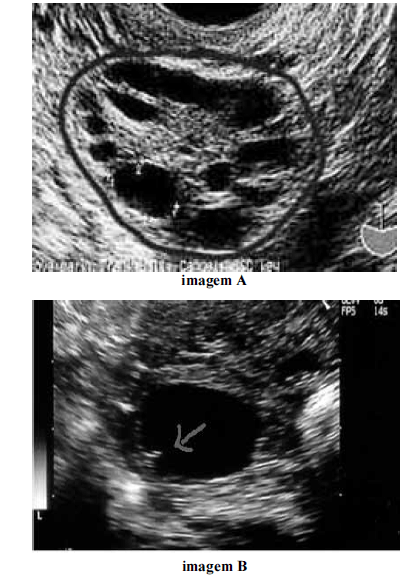

Considerando as imagens ovarianas apresentadas acima, julgue os itens a seguir.

Em ciclos ovulatórios induzidos, o crescimento folicular mostra-se independente e assincrônico, ou seja, nem sempre o maior folículo avaliado em determinada data será o maior em avaliações subsequentes.